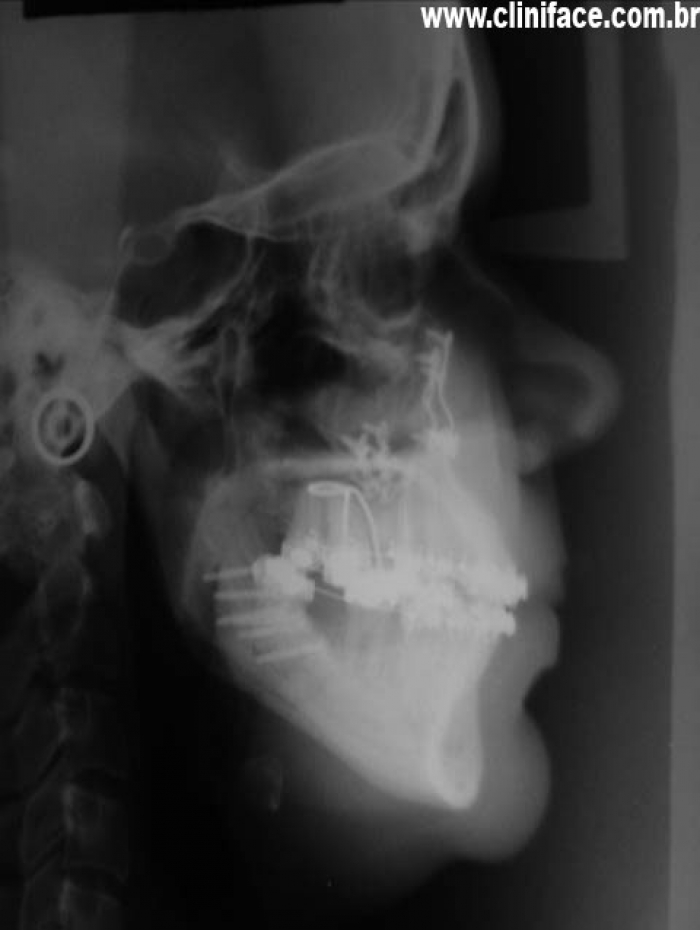

Telerradiografia inicial  - Clínica Cliniface

Telerradiografia inicial